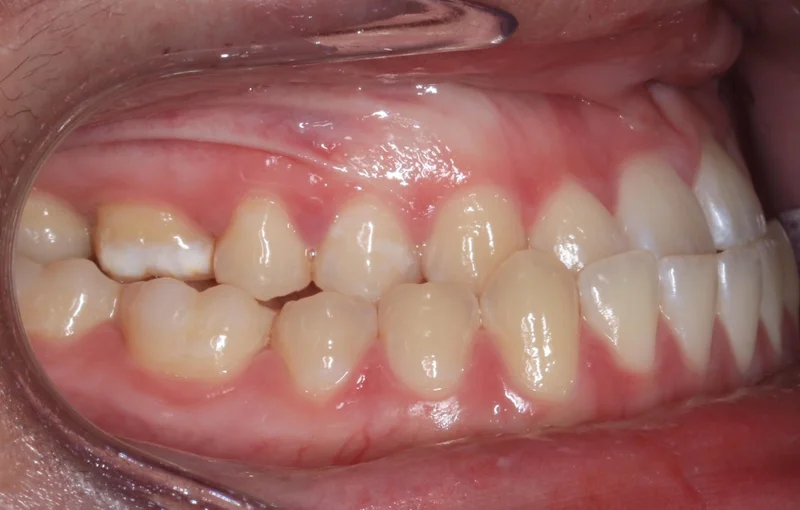

Case #90850 | 18 - 29 | Female

This young woman in Las Vegas came to us with a severe class III malocclusion (underbite) and the only option to correct her bite was with extractions on the upper arch and orthognathic surgery with an oral surgeon. She needed to have two teeth extracted first on the upper arch as part of the presurgical orthodontics to correct the severe proclination of the upper incisors. We first decompensated for this proclination by uprighting the upper incisors and closing the extraction space, which actually makes the overjet worse prior to surgery. She then had a double jaw surgery, including a Le Fort maxillary advancement as well as a mandibular setback. After about 6 weeks of post-surgical healing, she resumed orthodontic treatment to finish up. Her total treatment time was 27 months.

Right Buccal

Right Buccal - After Treatment

After